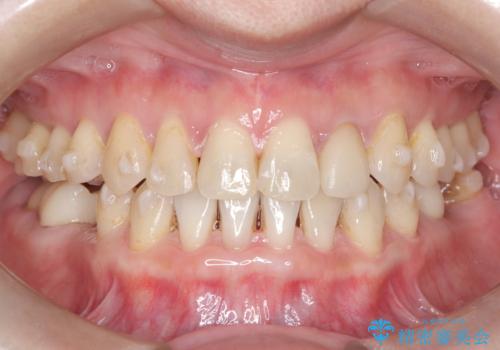

- 歯と歯の間に大きなスペースがある「空隙歯列(すきっ歯)」と、一部の歯が欠損していることによる噛み合わせの不安定さを主訴にご来院されました。

精密検査の結果、全体の隙間を閉じるだけでは適切な咬合バランスが得られないため、まずはインビザラインを用いて歯の位置を理想的な場所へと整える計画を立案しました。矯正によって欠損部位に適切なスペースを確保した後、その部分にインプラントを埋入することで、審美性と機能性の両立を目指しました。